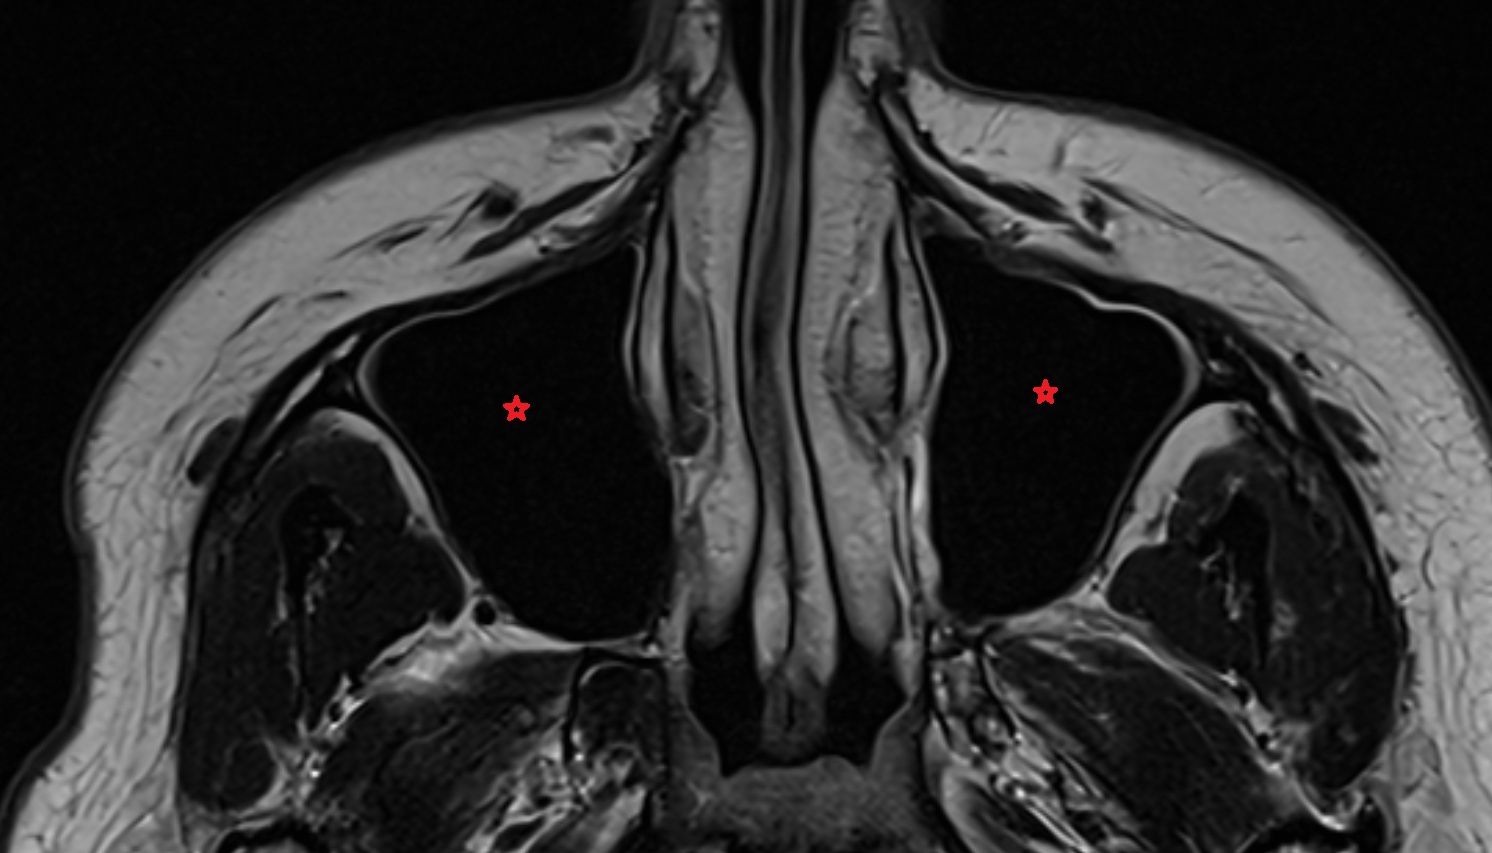

- Orbital part of optic nerve

- Vitreous chamber of eyeball